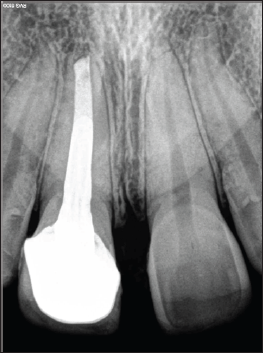

A 19year old female reported to New Al zahir Dental Clinic with chief complaint of unaesthetic appearance and pain in previously treated right upper front tooth. She gave a history of trauma 8 years ago, due to fall in house while playing with siblings and the fractured tooth segment was lost. The tooth was asymptomatic but observed tooth discoloration after 14 days of trauma. She was concerned for unaesthetic appearance and discoloration of tooth. Hence, undergone treatment by the family dentist, where pulpotomy was performed followed by aesthetic composite restoration. She was not pleased with composite restoration hence; a metal ceramic crown was provided for esthetic satisfaction. She does not recollect any sort of vitality testing done previously. She had observed an increase in gap between crown and gingiva in the first four years after placement of crown, then after its static. She is getting pain in the same tooth since 2 weeks. Clinical examination revealed, red edematous gingiva, accelerated gingival recession with round and thick gingival margin around maxillary right central incisor (Figure 1). Thermal and electric pulp testing revealed non-vitality for maxillary right central incisor. Radiographic investigation revealed an attempt for cervical pulpotomy was made but ended up presenting a periapical lesion having restricted root formation with an open apex (Figure 2).

Figure 2.

Management initiated with removal of metal-ceramic crown using a crown remover. Pain management for non-vital immature tooth was done following protocols in accordance to the previous reports through root canal therapy with apexification [4]. As a definitive restoration post endodontic treatment, a metal ceramic crown with a collarless design was given (Figure 3). After 1 year follow-up, gingival inflammation has completely resolved and presented normal form of gingival margin which is thinner and sharper (Figure 4). A periapical radiograph was exposed and it revealed, continuity in lamina dura and consistent width of periodontal ligament space, suggests healing of periapical lesion (Figure 5).

Figure 5.